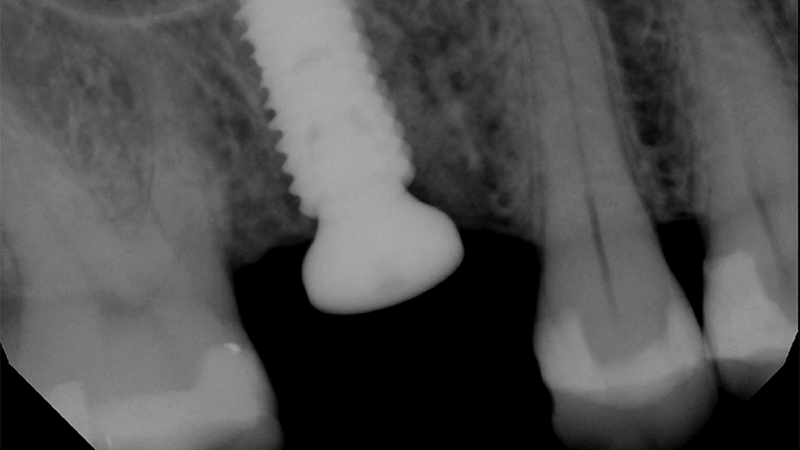

The First Surgical Robot Designed for Dental Implant Surgery, Yomi®, Surpasses 1000 Implants

Since 2000 more than 4 million robotic-assisted surgeries have taken place across multiple medical specialties including Cardiovascular, Neurology, and Orthopedics. Until the launch of Yomi, the first and only FDA cleared robot-assisted dental surgery system, dentistry has not been able to benefit from this revolutionary technology. Successfully placing dental implants requires careful pre-operative planning and a high … Read more